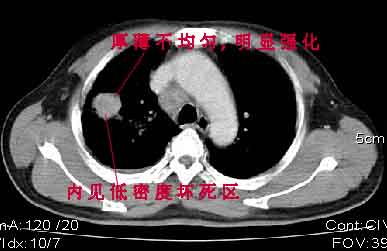

该病例我的诊断意见:右肺上叶周围型肺癌伴纵隔和右肺门淋巴结增大和右肺上叶阻塞性肺炎{病灶周围致密影以近肺门侧明显!}。右侧少量胸腔积液。

一. 1)症状有无发热及慢性过程.2)化验室检查?3)有无tb接触史?二.右肺上叶见片团状影,边界欠清,外侧方见一结节状软组织影,密度欠均匀,内可见低密度坏死区.周围强化明显,肺内见纤维索条影,局部胸膜增厚,但无明确胸膜凹陷.上叶支气管壁增厚,肺门及纵隔淋巴结增大.右侧胸腔少量积液.诊断意见:1右肺上叶慢性感染性疾病(肺tb?)伴肺门,纵隔淋巴结大.右胸少量积液.右肺上叶结节影多为tb球?2右肺上叶周围型肺ca伴肺门,纵隔淋巴结转移待排.右肺上叶炎变(肺门及纵隔淋巴结压迫).右胸少量积液.等待随返结果.